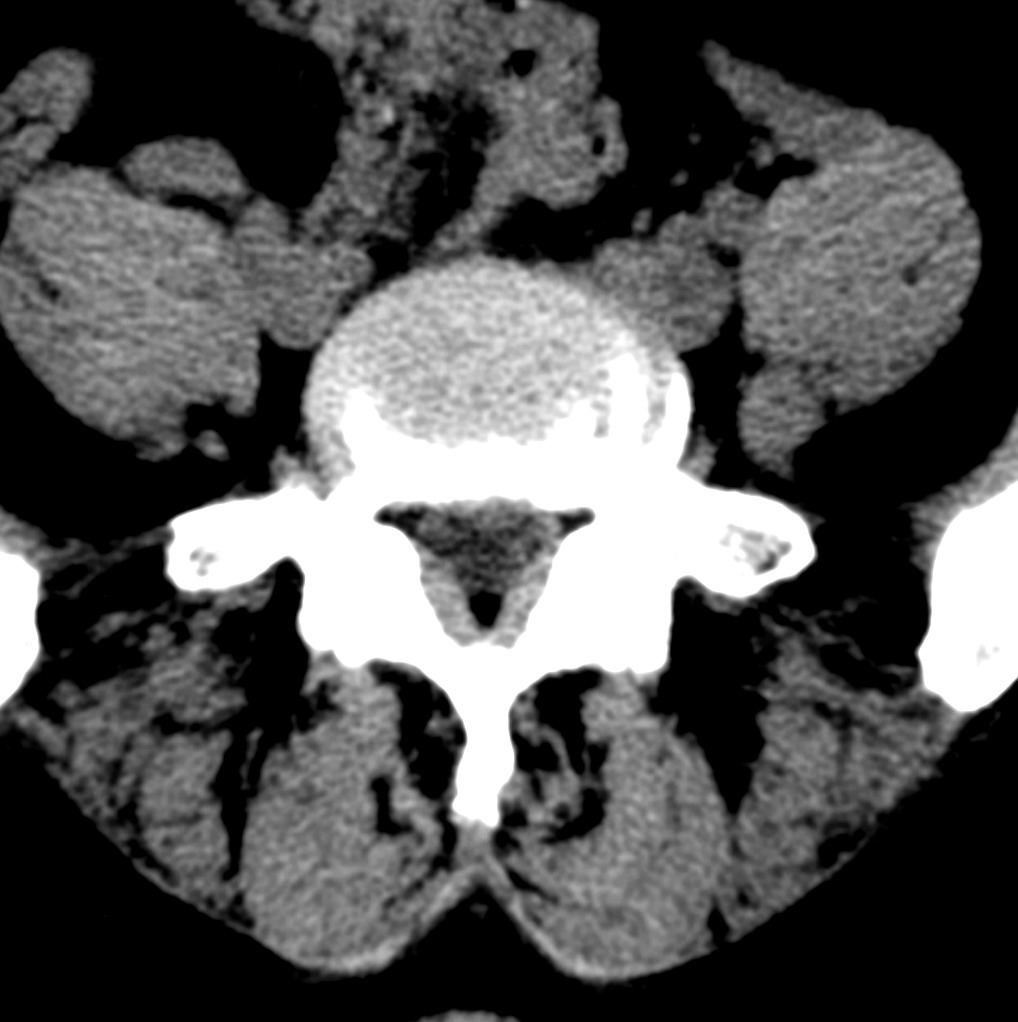

标题: CT19570:是否为腰脱? [打印本页]

标题: CT19570:是否为腰脱?

可以定腰脱否?

大于椎体的环状软组织影,椎间盘膨出

椎间盘膨出伴突出

双边征,考虑滑脱。

椎间盘突出

椎间盘改变并不是很明显,黄韧带似乎有肥厚,